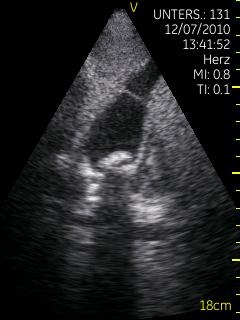

Vscan临床图片 腹部